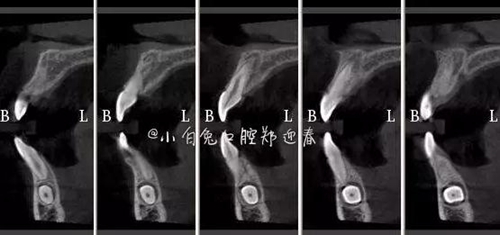

CBCT顯示

設(shè)計冠切的位置

橫斷牙冠,注意深度的把控

為了減少骨創(chuàng),“T”型分割牙冠

同時在剩余的根部斷面4MM下,預(yù)備2MM的溝槽,通過剝離子的三角尖端將牙體推出